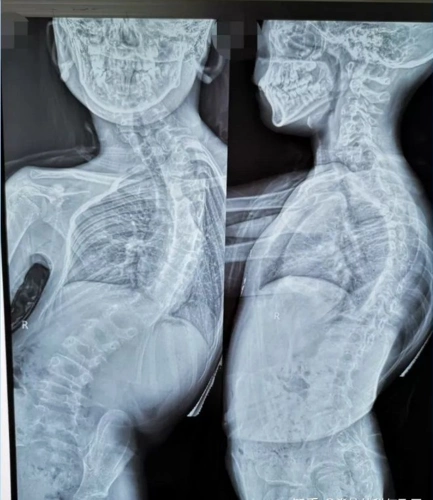

小儿脊柱侧弯 - 好大夫在线